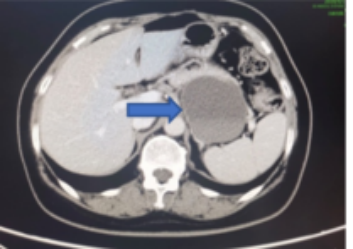

2010年11月12日患者接受了第1周期的含铂化疗治疗(紫杉醇+卡铂)。术后20天,患者双下肢肿胀逐渐加重,伴发热,外院行超声考虑双下肢静脉血栓,CT不除外肿瘤复发(图1)。随后收入血管外科予溶栓抗凝治疗2天后,双下肢肿胀明显加重。

图1 术后20天外院CT检查结果